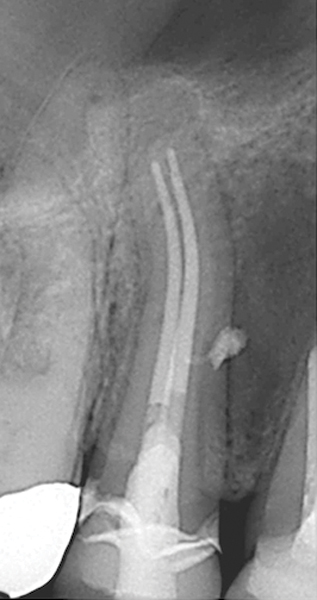

Figure 19. Preoperative radiograph of a case demonstrating apical periodontitis. Courtesy of Dr. Allen Ali Nasseh.

Figure 19

Figure 20. Immediate postoperative radiograph. Courtesy of Dr. Allen Ali Nasseh.

Figure 20

Figure 21. 5-year follow-up with complete healing. Courtesy of Dr. Allen Ali Nasseh.

Figure 21